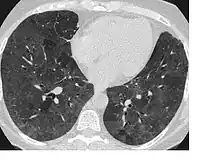

Infiltrat en verre dépoli

On appelle infiltrat en verre dépoli une image pathologique qu'on peut voir sur une radiographie pulmonaire ou en tomodensitométrie.

C'est un aspect de halo aux limites floues, focalisé ou diffus, sans systématisation.

L'arborescence vasculaire reste bien visible au sein de cet infiltrat.

Le grossissement de l’image révèle un aspect réticulé parsemé de très fins micronodules, ou un seul de ces aspects.

Cette image correspond à une hypertrophie inflammatoire du tissu interstitiel (parois alvéolaires et interstitium interlobulaire) qui devient radiologiquement individualisable.

Elle peut aussi correspondre au comblement partiel de la lumière de certaines alvéoles par des débris cellulaires ou par des membranes hyalines.